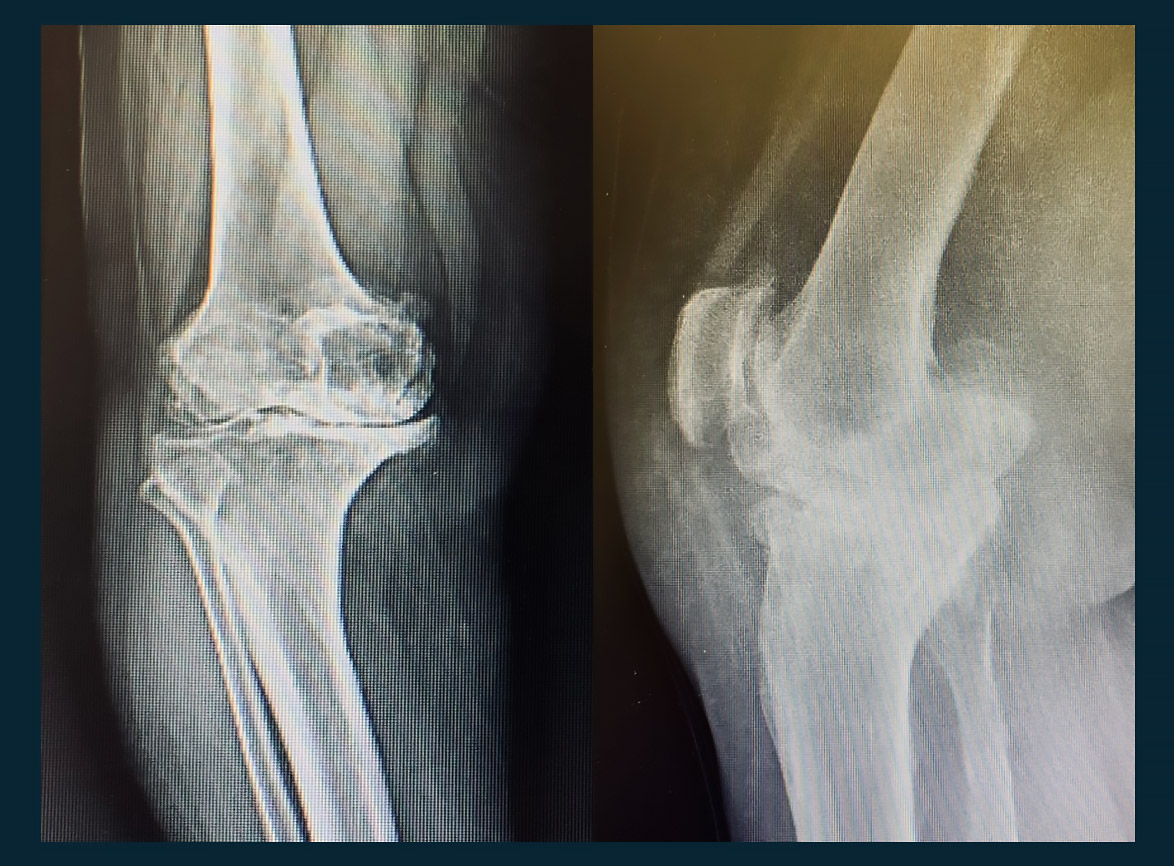

(DİZ EKLEMİ OSTEOARTRİTİ)

Gonartroz, diz eklemindeki kıkırdak dokusunun zamanla aşınması ve dejenerasyonu sonucu ortaya çıkan bir tür eklem hastalığıdır. Bu durum genellikle yaşlanma süreciyle ilişkilidir, ancak bazen genetik faktörler, aşırı kilo, eklem travmaları veya belirli meslekler gibi diğer faktörler de etkili olabilir. Gonartroz, diz ekleminde ağrı, şişlik, sertlik ve hareket kısıtlılığı gibi belirtilerle kendini gösterir.

Bu süreçlerin neticesinde, diz ekleminde ağrı, şişlik, sertlik ve hareket kısıtlılığı gibi gonartroz belirtileri ortaya çıkar. Tedavi genellikle bu süreçleri yavaşlatmaya, semptomları yönetmeye ve hastanın yaşam kalitesini artırmaya odaklanır.